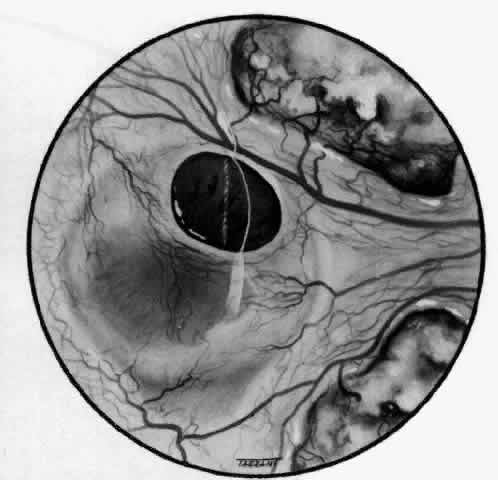

With the increasing use of anterior segment fluorescein angiography in the early detection of severe necrotizing disease of the sclera, it is necessary to have an understanding of the normal anatomy of the vasculature of the anterior segment of the eye.3–5 The blood supply to this region is enormous, being derived from the anterior ciliary arteries, but with extensive collateral arterial anastomoses to the posterior ciliary arteries at the root of the iris (Fig. 1). The anterior system is readily visible with the slit lamp and by anterior segment fluorescein angiography, especially if the eye is inflamed, and its recognition is of vital importance in the differentiation of episcleral and scleral conditions. The separation and displacement of these vascular layers give the most important clinical clues to the site and, hence, the severity of the inflammation. On slit lamp examination, three layers of vessels are readily visible. The conjunctival plexus, which is the most superficial layer of vessels, can be moved over the underlying structures. The superficial episcleral capillary plexus (Fig. 2) is a radially arranged series of vessels lying within the parietal layer of Tenon's capsule. The vessels in this layer anastomose at the limbus with the conjunctival vessels, with other members of the same plexus, and with the deep plexus. The deep episcleral capillary network (see Fig. 2) is closely applied to the sclera in the visceral layer of Tenon's capsule. The vessels anastomose freely with each other, forming a syncytium. The large vessels to and from the intrascleral plexus traverse the episclera near the insertions of the muscles. The conjunctival and superficial episcleral vessels can be blanched with 1:1000 epinephrine or 10% phenylephrine, but the deep vessels are affected slightly. This is of considerable assistance when attempting to differentiate deep and superficial inflammation.

Fig. 1. Anterior view montage of a cynomolgus monkey ocular casting with Tenon's and episcleral vessels removed. The anterior ciliary arteries (ACA) arborize at the limbus and interconnect via their lateral branches to form the episcleral circle. (CM, ciliary muscle capillary bed; CV, choroidal veins; EC, episcleral circle. (Original magnification, X20). (Morrison JC, van Buskirk EM: Anterior collateral circulation in the primate eye. Ophthalmology 90:707, 1983)

Fig. 2. The normal relationships of the capillary networks that can be seen with the slit lamp are a conjunctival (easily mobile) network, a superficial episcleral network in the parietal layer of Tenon's capsule, and a deep episcleral plexus closely applied to the sclera. These relationships are much more obvious in inflamed eyes (see Figs. 13, 14, and 30). (Watson PG, Hayreh S, Awdry P: Episcleritis and scleritis. Br J Ophthalmol 52(3):278– 279, 1968)